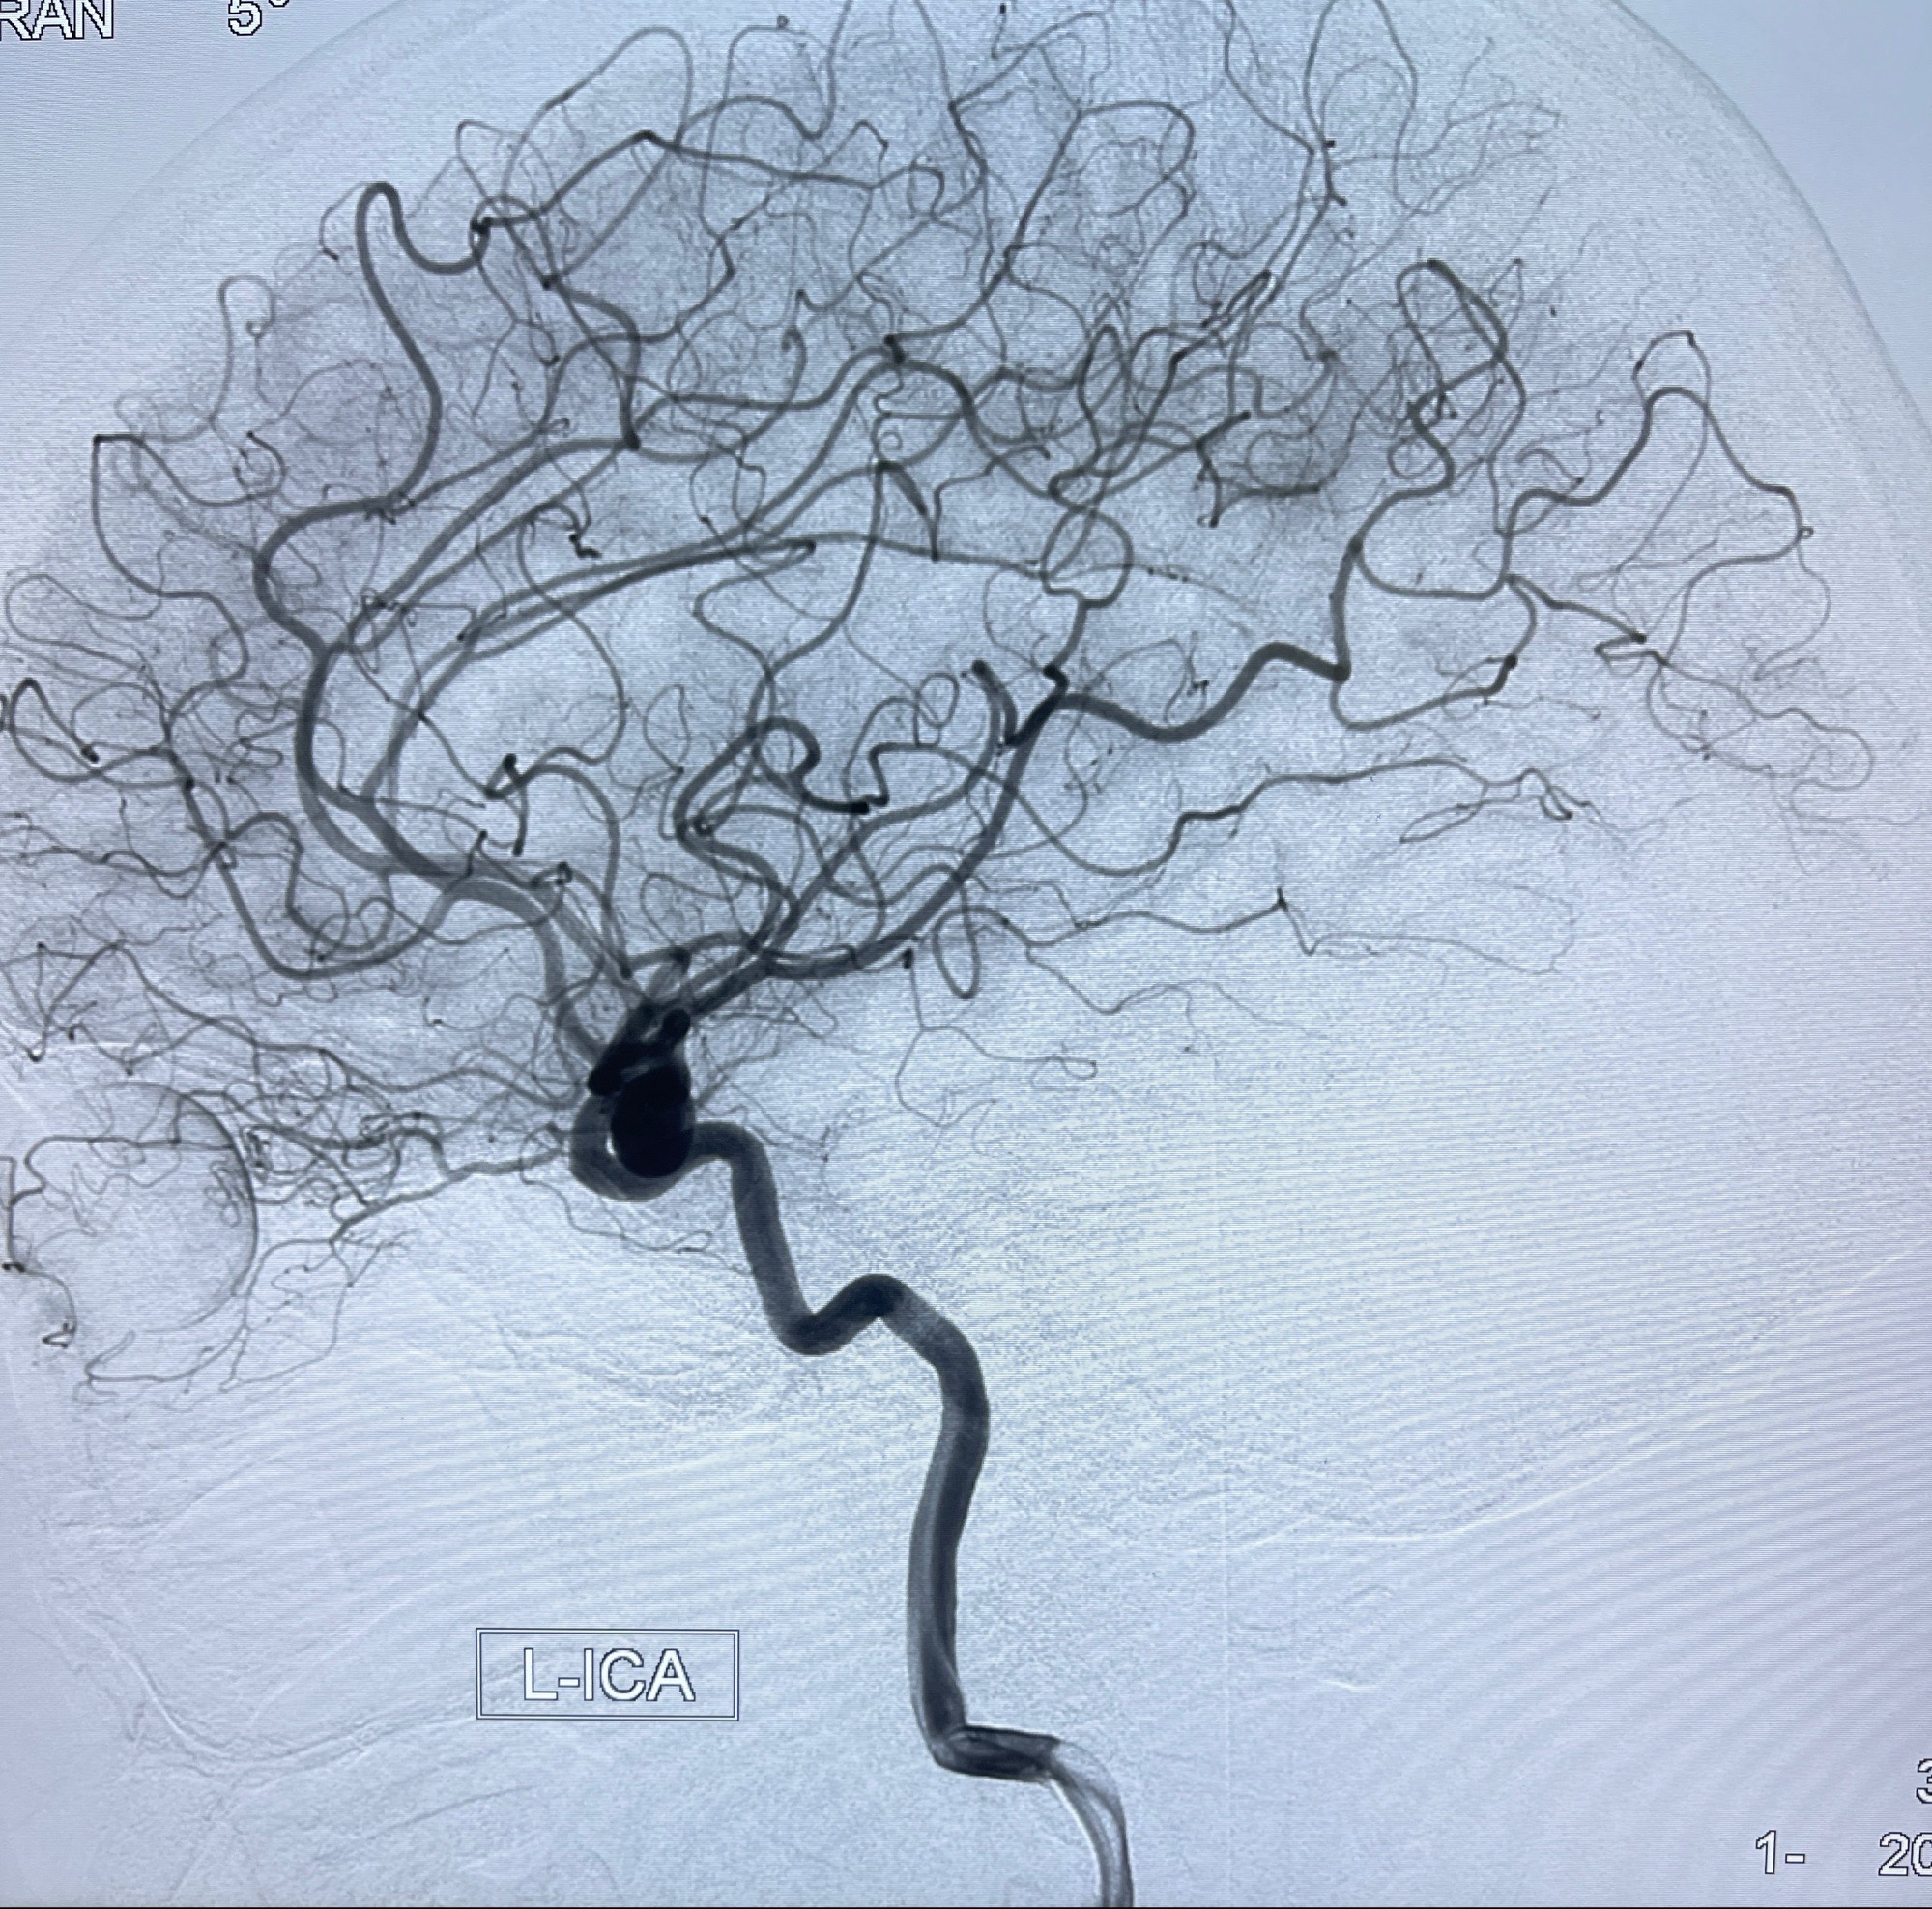

2023-08-30DSA:左侧颈内动脉眼动脉动脉瘤,约3*9.2*7.3mm大小